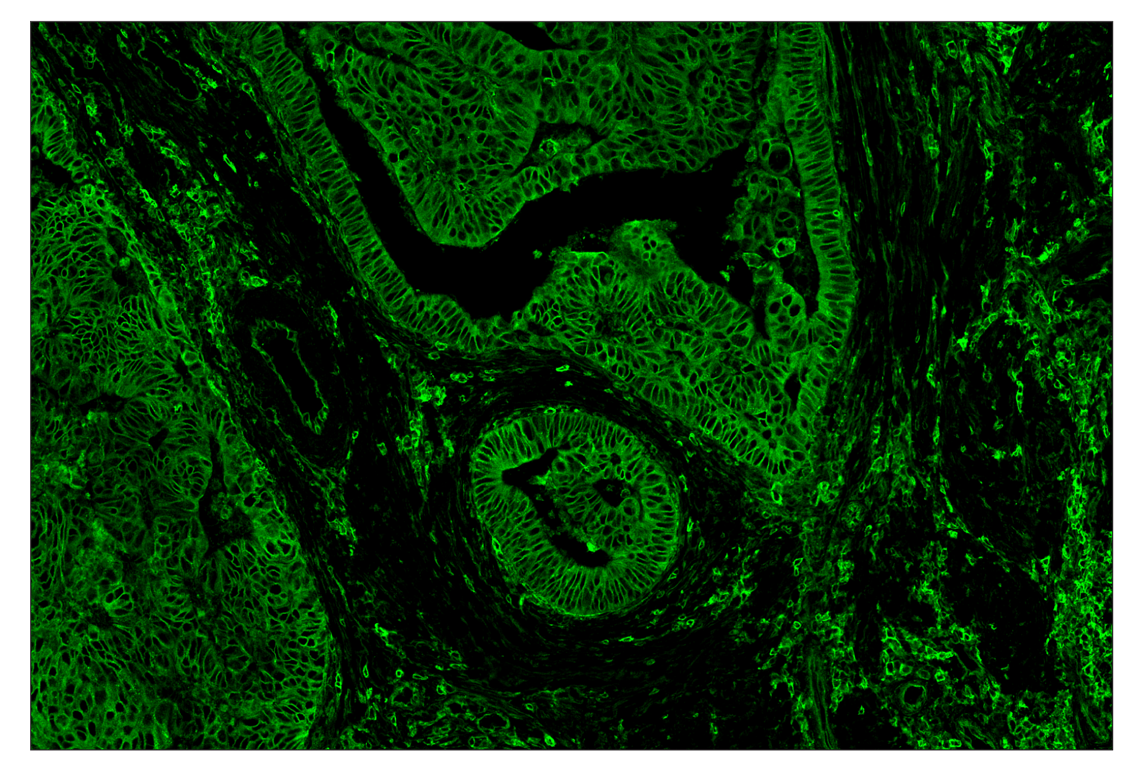

Immunohistochemistry Image 1: MHC Class I (EMR8-5) & CO-0082-647 SignalStar<sup>™</sup> Oligo-Antibody Pair

SignalStar™ multiplex immunohistochemical analysis of paraffin-embedded human colorectal adenocarcinoma using MHC Class I (EMR-8) & CO-0082-488 SignalStar™ Oligo-Antibody Pair #38418 (green). All fluorophores have been assigned a pseudocolor, as indicated. Staining was performed on the BOND RX autostainer by Leica Biosystems.